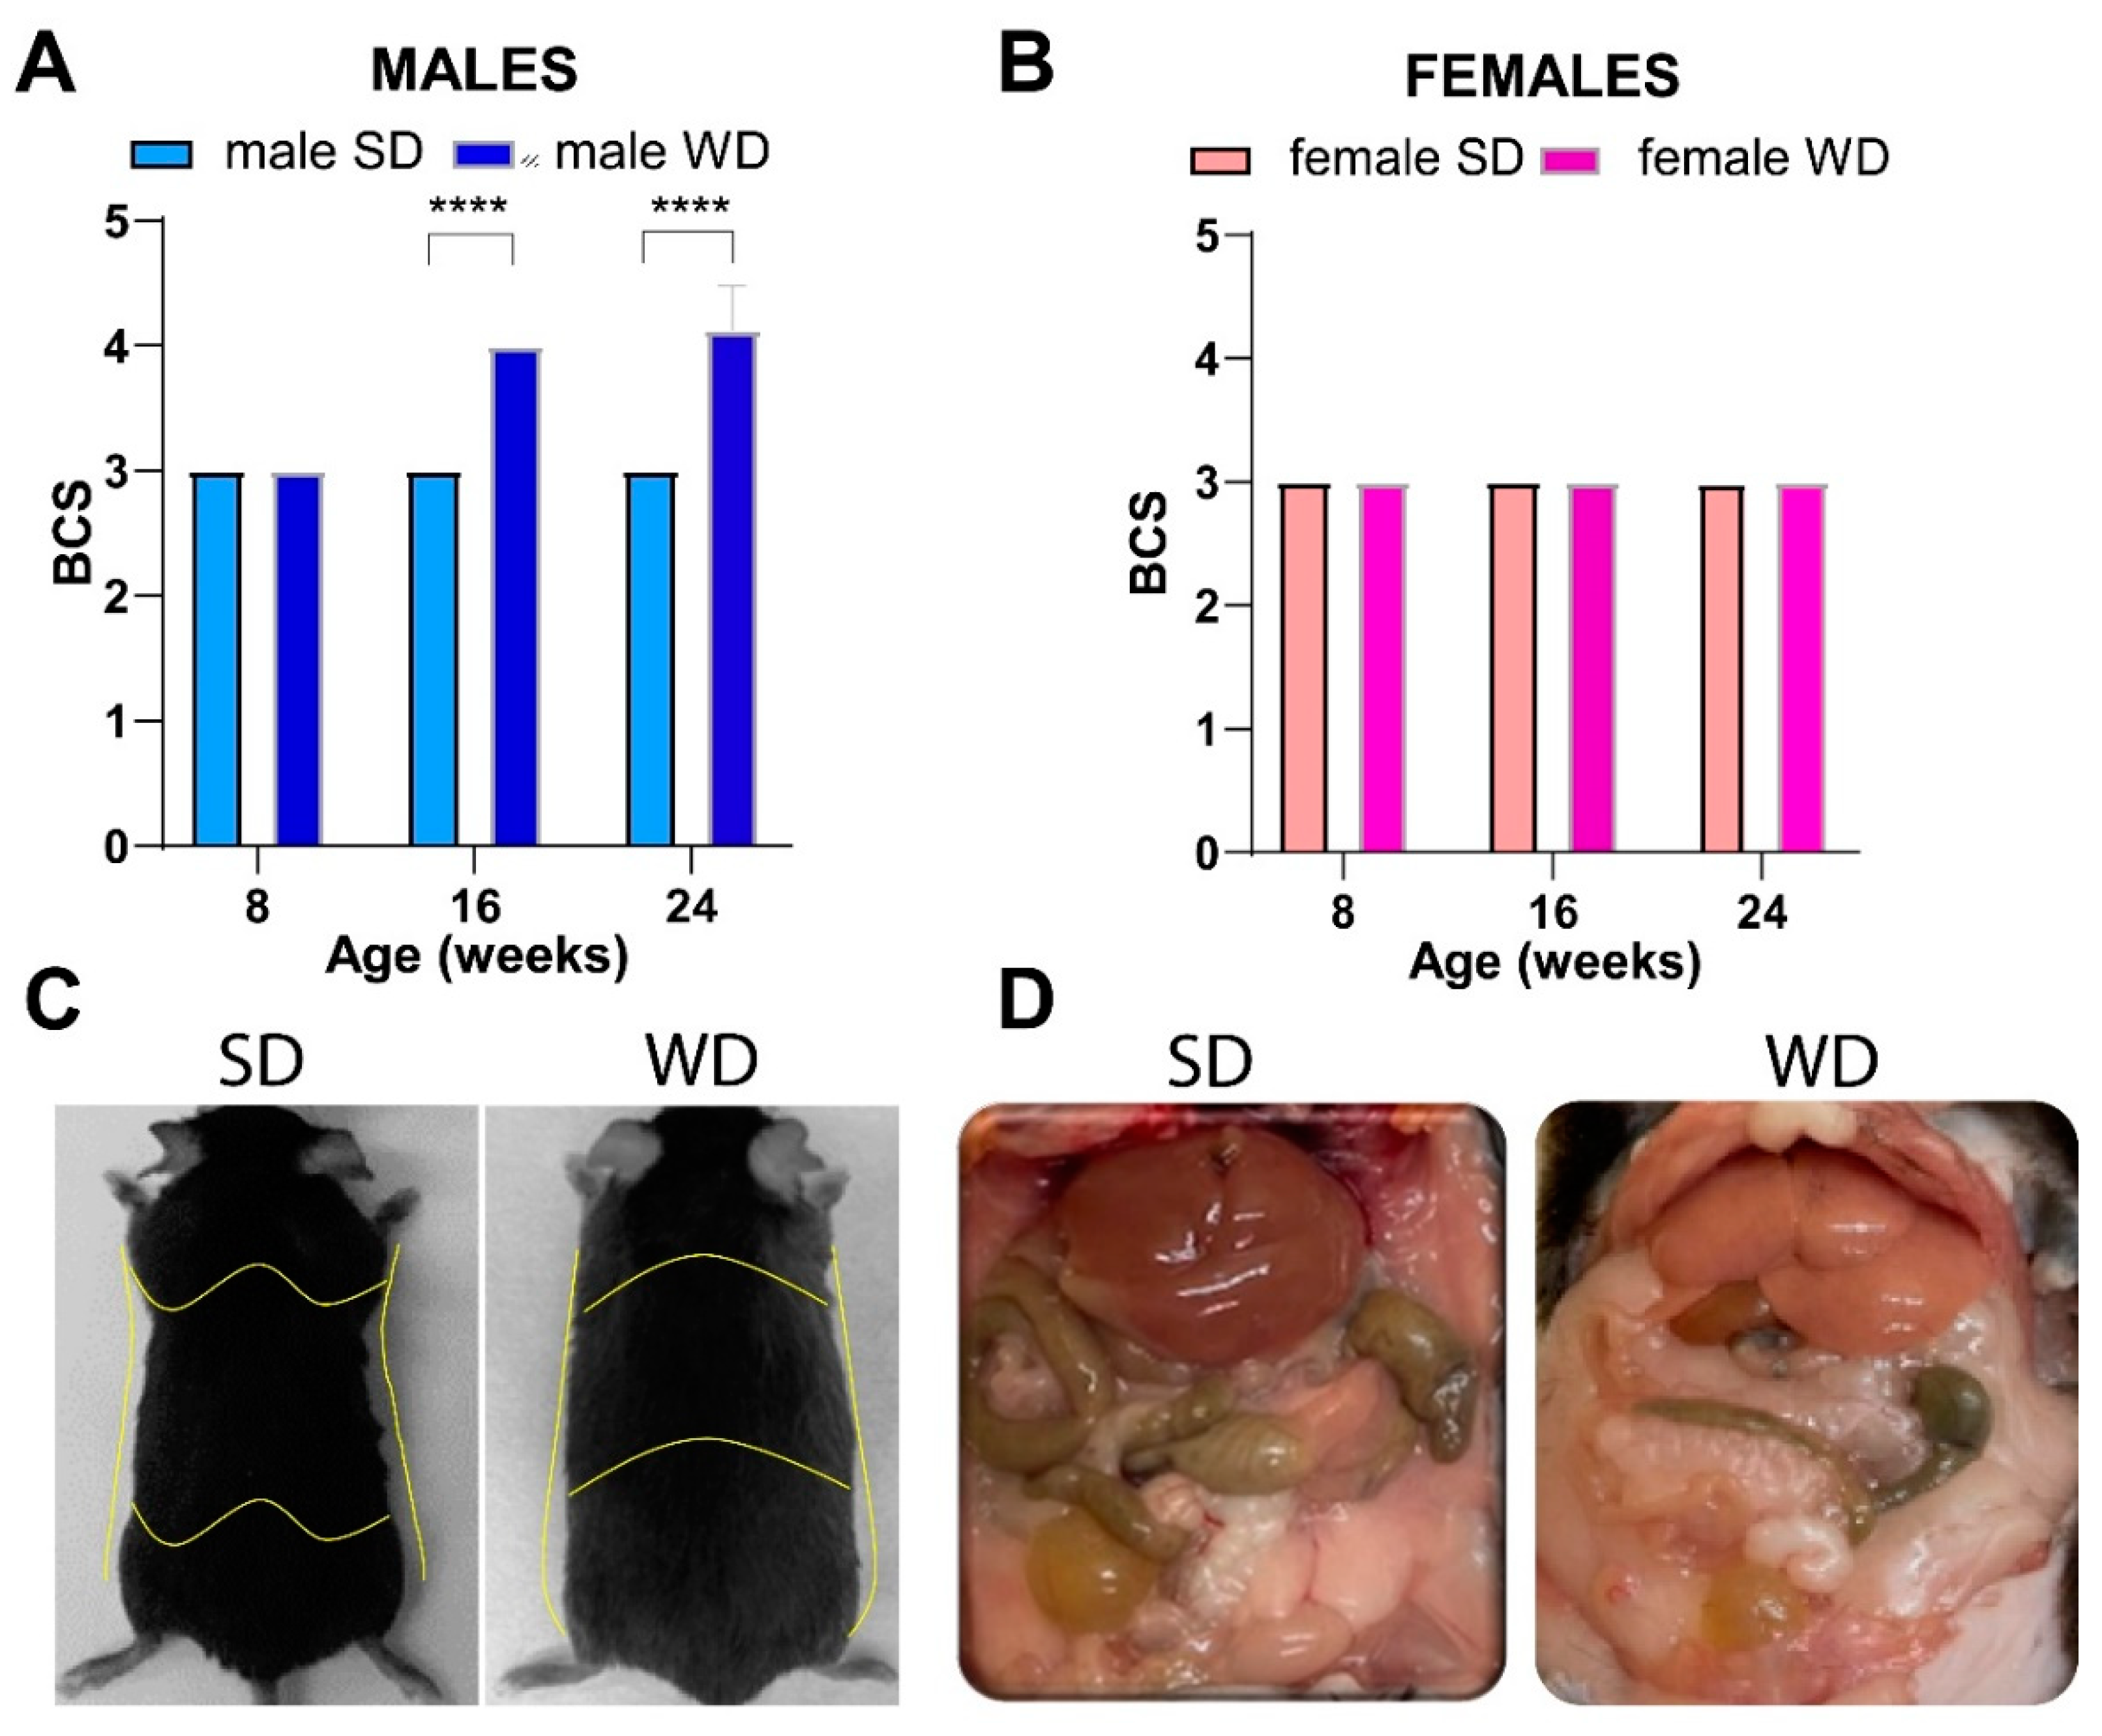

3.2. WD Influences Feeding Behavior in C57Bl/6J Substrain